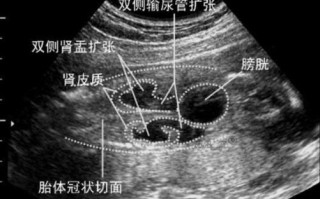

新生儿健康护理 新生儿肾盂分离5mm要紧吗? 核心结论(先给您吃一颗定心丸)对于10天新生儿来说,肾盂分离5mm是一个非常常见且绝大多数情况下完全正常的生理现象,通常无需过度担心,什么是肾盂分离?肾盂是肾脏中汇集尿液的“漏斗”部分,当尿液在肾脏内... 99ANYc3cd6 2025-11-29 1 #新生儿肾盂分离5mm严重吗 #新生儿肾盂分离5mm需要治疗吗 #新生儿肾盂分离5mm会自愈吗